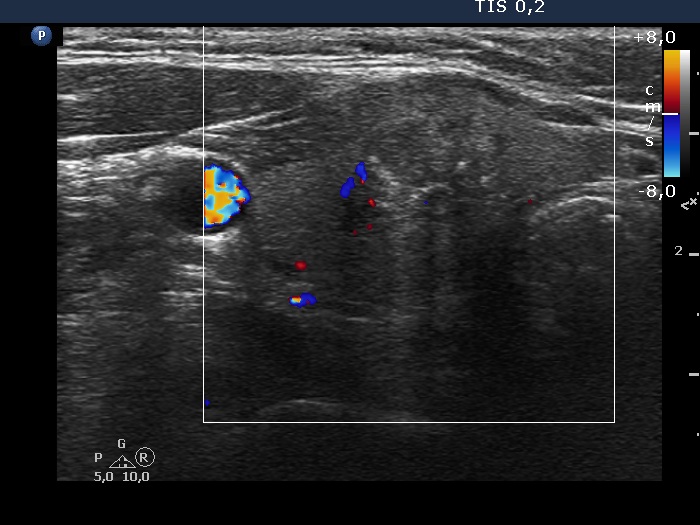

100 consecutive cases of papillary cancer - case 075 (ultrasonographic picture 7)

Right lobe, longitudinal scan

Right lobe, transverse view, color Doppler mode. The vascularization is scanty.